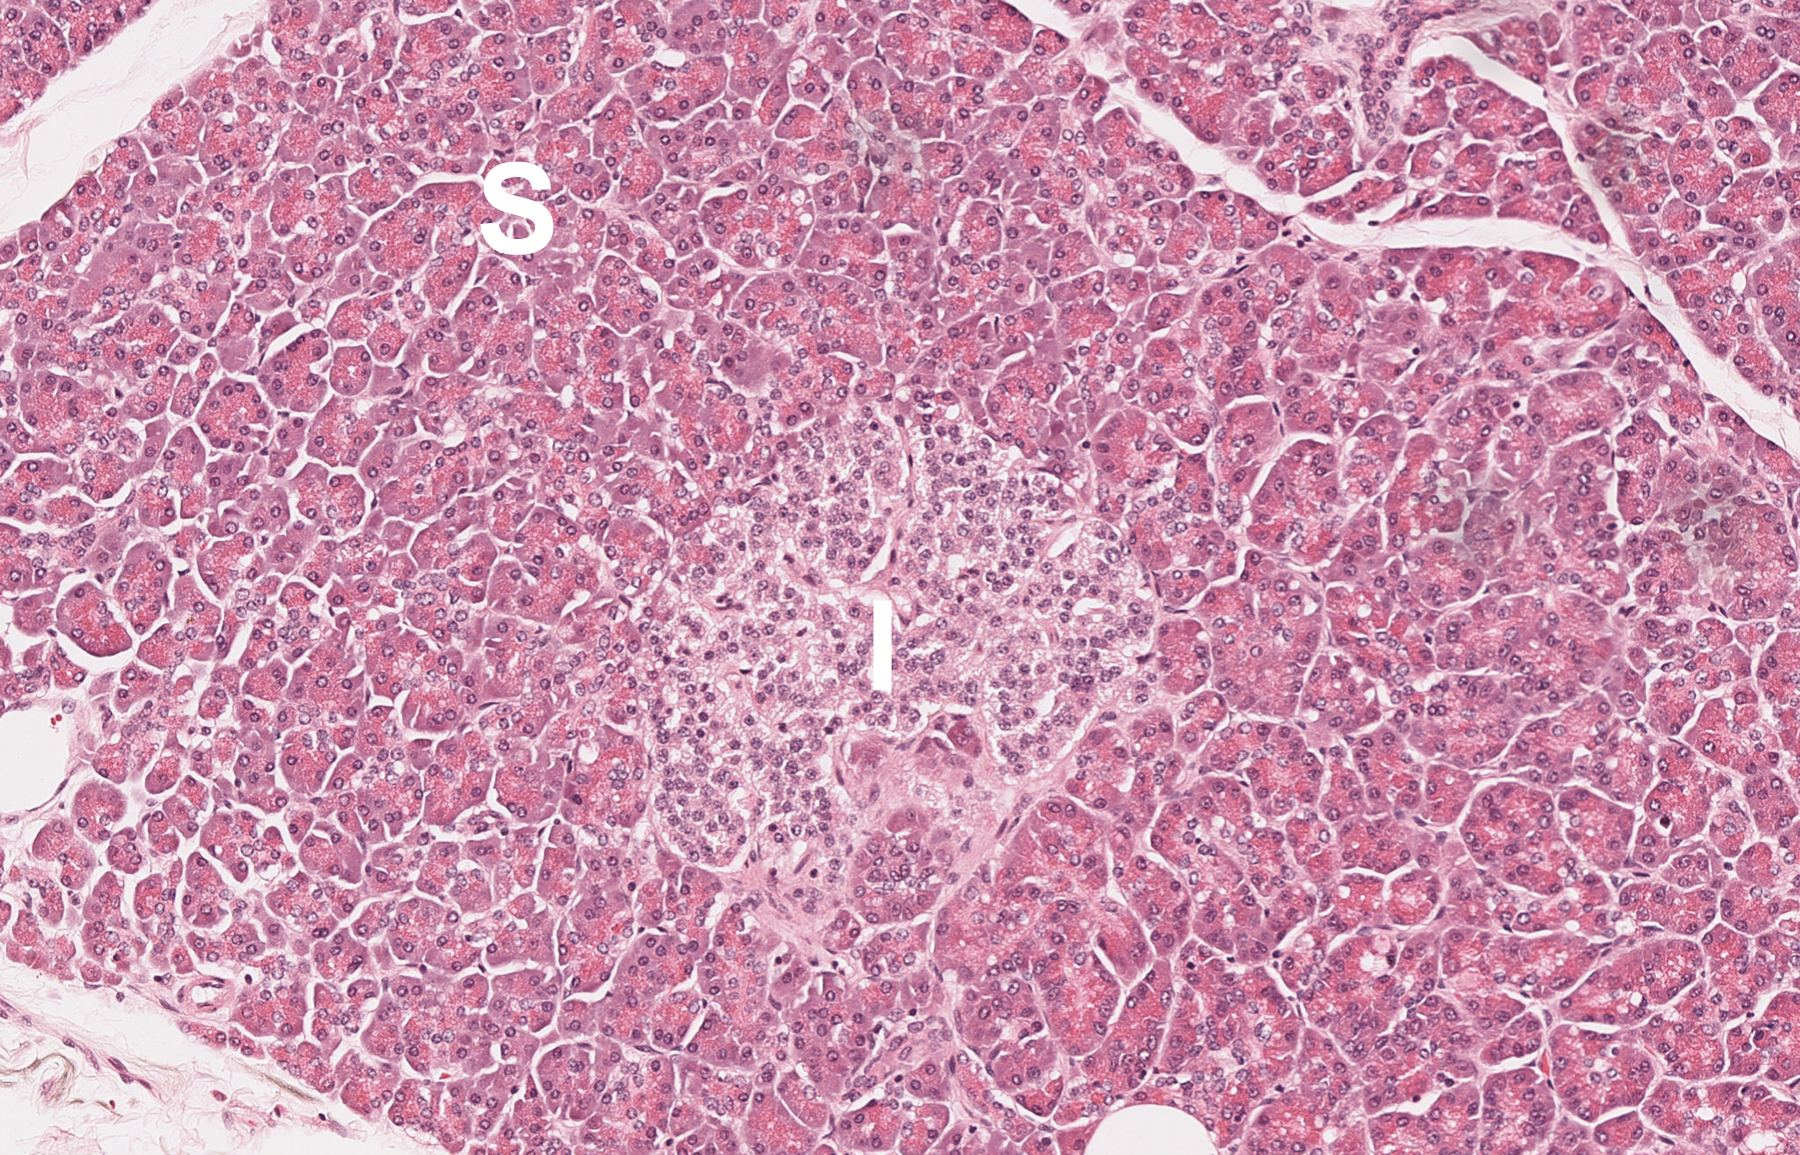

The pancreas has two major functions, one exocrine and the other endocrine. The first involves secretion of enzymes into the small intestine to aid in food digestion. The enzymes are made in serous cells, which secrete them via ducts that lead to the duodenum. They include trypsinogen (to digest proteins), amylase (for carbohydrates) and lipase (for fats). Pancreatic endocrine function is concerned primarily with control of glucose (sugar) metabolism via enzymes such as insulin and glucagon. These substances are made by cells located in small clusters known as Islets of Langerhans from which they are secreted directly into the blood, insulin causing a decrease in blood glucose and glucagon an increase.

Below: Histologic appearance of normal pancreas (I- Islet of Langerhans; S- serous cells) and chronic pancreatitis (F- fibrosis; note loss of serous cells).